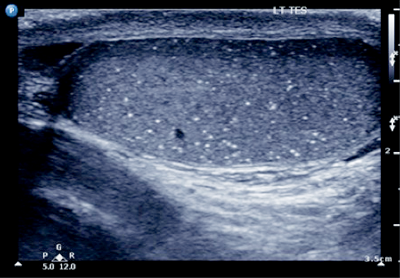

Case 2

- What is this pathology?

-

Microlithiasis.

Five or more echogenic foci per high powered view, in either or both testes.